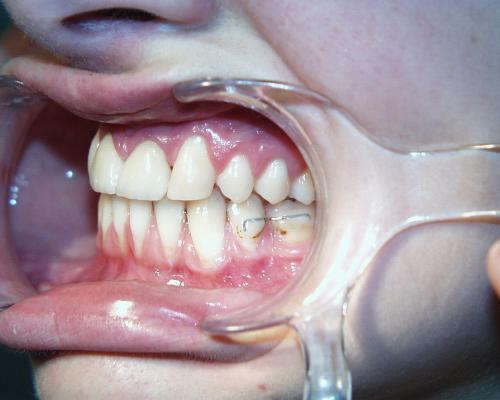

Vor der Behandlung

Fallbeispiel 7 ist ein besonders komplexer Fall. Die oberen mittleren Schneidezähne waren durch Stürze so stark vorgeschädigt, daß sie längerfristig nicht mehr erhalten werden konnten. Im Unterkiefer fehlten die zweiten (bleibenden) kleinen Backenzähne, die zweiten Milchbackenzähne standen daher noch im Kiefer. Es wurde beschlossen, die nicht erhaltungsfähigen oberen Schneidezähne und ausgleichend die beiden noch im Mund befindlichen Milchbackenzähne im Unterkiefer zu entfernen. Im Oberkiefer sollten die seitlichen Schneidezähne an Stelle der mittleren Schneidezähne bewegt und im Unterkiefer ein Lückenschluß ausgeführt werden.